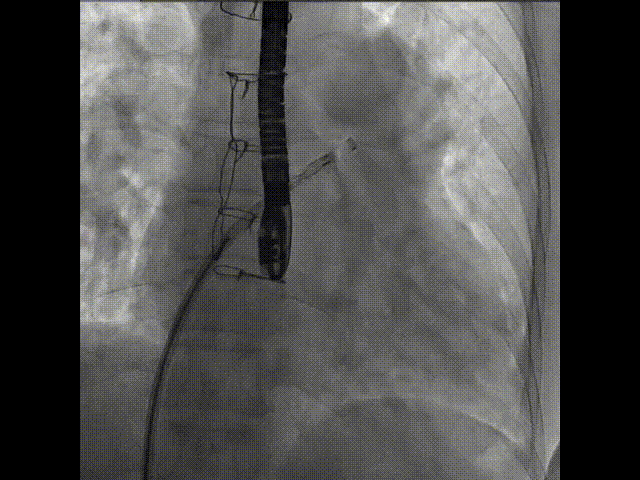

術(shù)中首先在局麻下穿刺股動(dòng)脈、股靜脈,完成心導(dǎo)管檢查評(píng)估后轉(zhuǎn)為全麻,在食道超聲引導(dǎo)下穿刺房間隔,穿刺成功后將加硬導(dǎo)絲送入左上肺靜脈建立軌道,根據(jù)患者病情行球囊預(yù)擴(kuò)張后植入6mm孔徑房間隔造孔支架,經(jīng)透視及食道超聲評(píng)估支架左右盤展開良好,夾持于房間隔兩側(cè),固定穩(wěn)定、位置良好,食道彩超顯示房水平右向左為主分流,分流孔直徑符合預(yù)期大小,心導(dǎo)管檢查評(píng)估達(dá)到預(yù)期效果,釋放造孔支架。術(shù)后12h患者下床活動(dòng),恢復(fù)順利,擬于近日完善術(shù)后評(píng)估后出院。